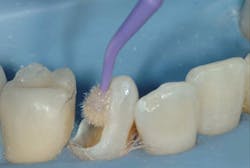

At this point in the treatment, patients should be able to begin a slow and relatively inexpensive way to restore the teeth that had provisional restorations placed in them. Although the carious lesions are large and would be better restored with crowns, consider the following procedure due to the patient's financial limitations. Use build-up techniques on the affected teeth with conventional esthetic restorative materials instead of the relatively unesthetic typical build-up resin-based composites. Most patients have dental benefit plans. Bill these restorations as build-ups (code 2950), not as final restorations. When a patient has adequate financial ability, crowns should be done.

The following images show a patient with limited finances but a strong desire to retain her teeth. The crowns present in the quadrant placed by a previous dentist show that the patient at one time had adequate finances for crowns.

The technique for building up restorations to restore deep carious lesions follows: